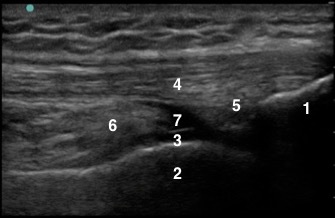

Knee Suprapatellar Recess with 30 degree Flexion Image

1. Patella (Superior Pole of the Patella)

2. Femoral Condyle of the Distal Femur

3. Trochlear Cartilage

4. Quadriceps Tendon

5. Quadriceps Fat Pad

6. Pre-femoral Fat Pad

7. Suprapatellar Recess